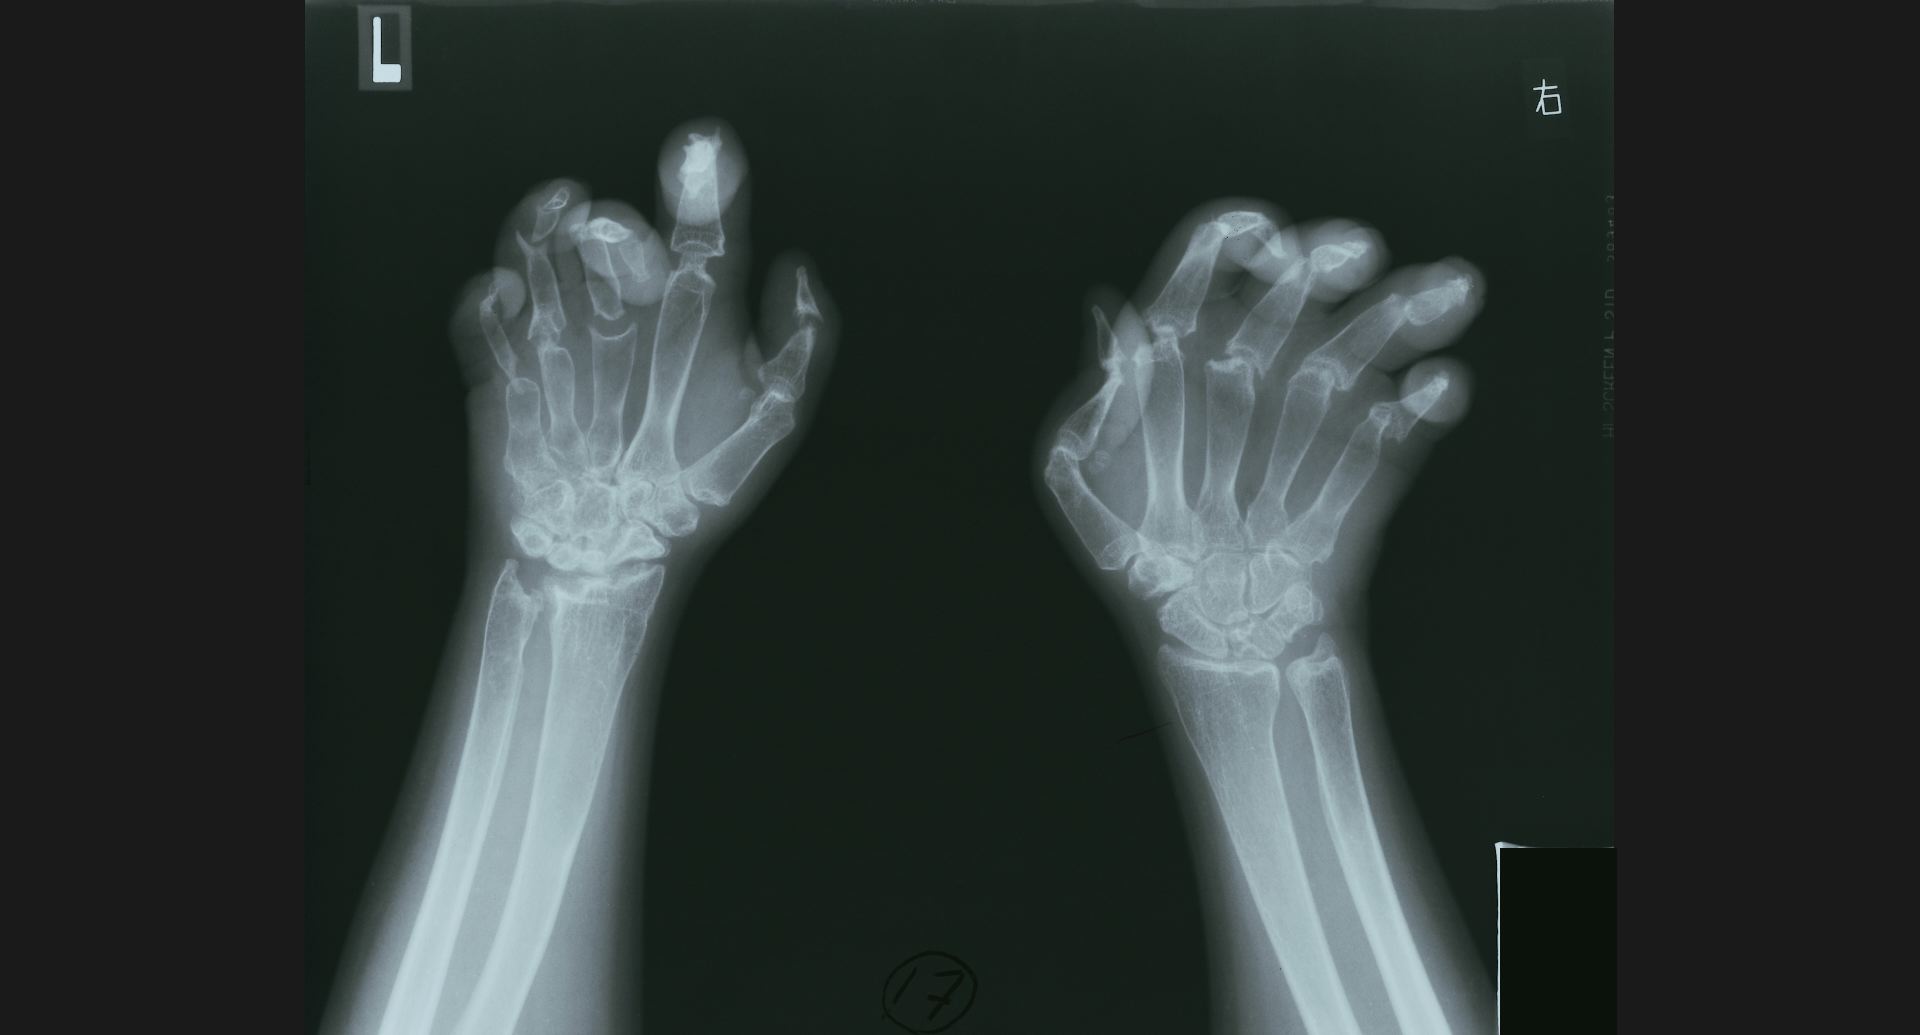

fig.17(81KB)

:Acro-osteolysisradius遠位端の骨梁。骨融解部。